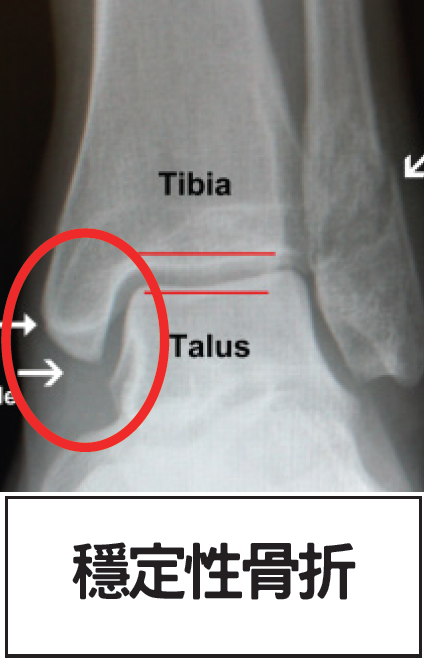

穩定性骨折: 若X光片上只見一條白色骨裂線,而骨頭位置沒有移位(如下圖),多屬穩定性骨折。